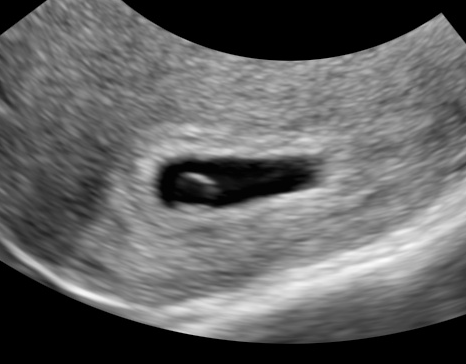

妊娠7週0日 7w0d の超音波 エコー 写真

超音波写真館 妊娠初期4 7週 超音波教室 ママニティ大百科

妊娠7週目 胎芽 胎嚢のエコー写真や大きさ つわりや流産 妊娠初期 All About